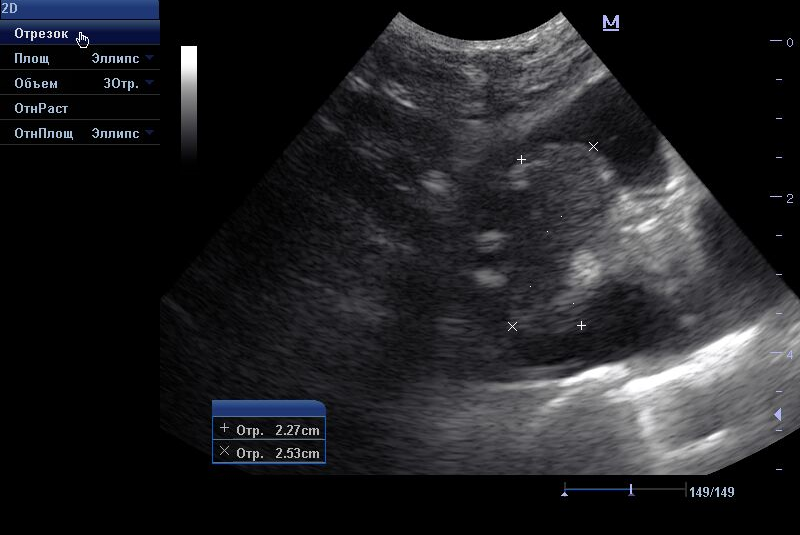

- Диагностика плеврального выпота;

- Диагностика гидроторакса;